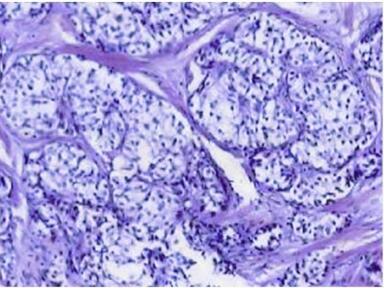

脾脏血管瘤(splenic hemangioma)(图3、图4)

图3 病理回报为脾脏血管瘤

图4 病理回报为脾脏血管瘤